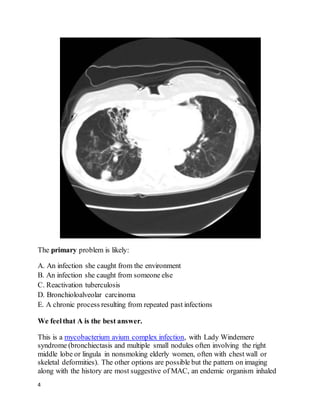

This is a mycobacterium avium complex infection, with Lady Windemere

syndrome (bronchiectasis and multiple small nodules often involving the right

middle lobe or lingula in nonsmoking elderly women, often with chest wall or

skeletal deformities). The other options are possible but the pattern on imaging

along with the history are most suggestive of MAC, an endemic organism inhaled

from soil or water. Her bronchiectasis could perpetuate her cough and hemoptysis;

however, she also has many nodules that are indicative of ongoing infection as the

primary process.Nontuberculous mycobacteria (NTM) also include M. kansasii,

rapidly growing mycobacteria (RGM), and numerous less common species.

Nonpathogenic airway colonization by these organisms is frequently incidentally

discovered and must be differentiated from infection. NTM infection commonly

causes a TB-like pattern (upper lobe cavitary disease); hypersensitivity

pneumonitis (ground glass and centrilobular nodules, sometimes with a mosaic

pattern), or the pattern seen here (nodular bronchiectasis with or without

fibrocavitary disease), along with low-grade nonspecific symptoms usually

including cough and fatigue.